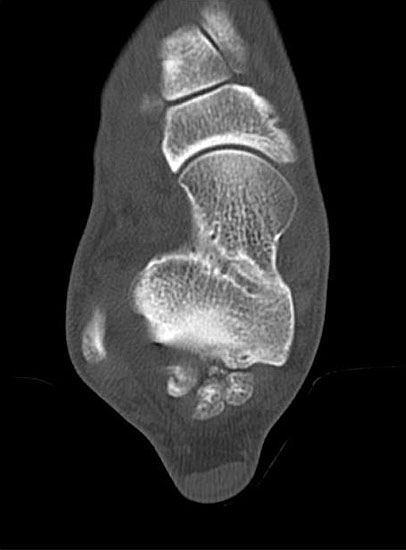

Abbildung Nr. 19-22

Knochenresektat sowie präoperatives CT (Sagittal- und Transversalebene) und intraoperative Bildwandlerkontrolle im seitlichen Strahlengang nach arthroskopischer Entfernung multipler Ossikel am dorsalen OSG/USG.

Abbildung Nr. 23 und 24, Video Nr. 4

Große osteophytäre Anbauten, welche die FHL-Sehne vollständig ummauern, sind ebenfalls sehr gut in der beschriebenen Technik adressierbar. Präoperatives CT und intraoperative Bildwandlerkontrolle im seitlichen Strahlengang (linke Seite).